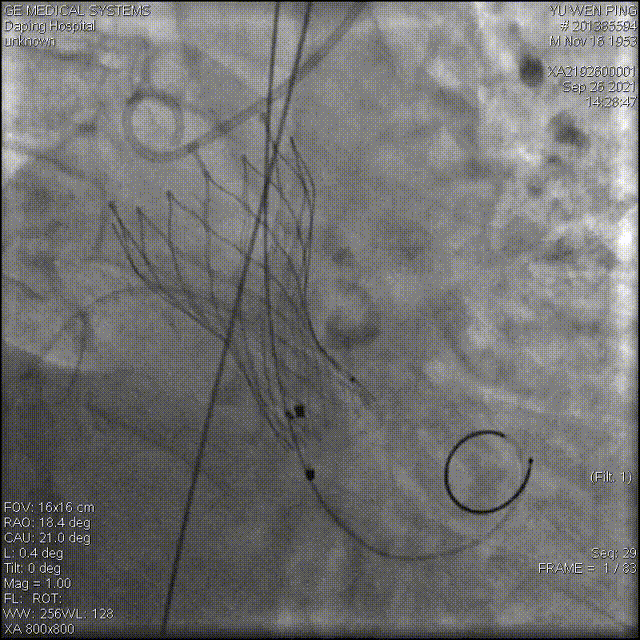

以 Seldinger法穿刺右桡动脉,行PCI后,使用PIG造影管行主动脉根部造影

22mm球囊预扩

造影确定输送器位置

高位释放瓣膜

受钙化挤压影响,瓣膜展开状态差,决定进行后扩

22mm球囊后扩

经后扩,支架展开形态良好